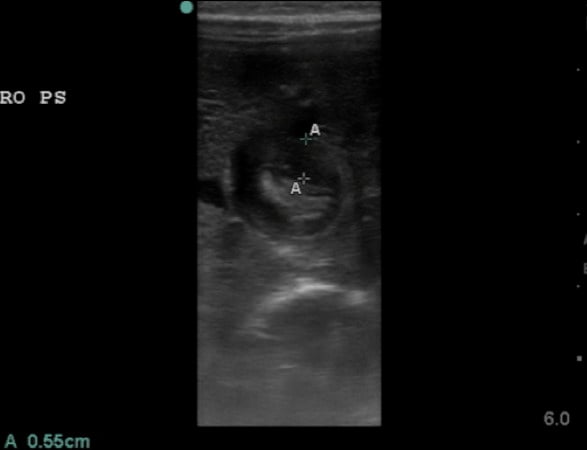

- Thickness of the pyloric muscle can be measured in the long or short axis view

- Figure 7. Hypertrophied pyloric muscle in short axis measuring 5.5mm

- A thickness of ³3mm is considered abnormal or hypertrophied